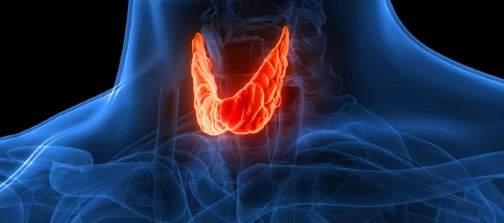

Lo que debes saber de la glándula tiroides

La tiroides es una glándula que pertenece al sistema endocrino; se encuentra en la cara anterior del cuello y tiene la forma de una mariposa.Esreguladaporlaglándulahipófisis,la cual produce TSH (hormona estimulante de tiroides) enviando la señal para que la glándula tiroideslibereprincipalmentehormonastiroideas: T4 (tiroxina) y T3 (triyodotironina), que tienen diversas funciones vitales en el organismo, ya queintervienenenlaregulacióndelmetabolismo y la temperatura corporal; el crecimiento; desarrollodelsistemanerviosoycontroldelritmo cardiaco;pesoyfertilidad.

Las alteraciones en la tiroides son más frecuentesenmujeresyenedadmediadelavida; sin embargo, pueden ocurrir en hombres y a cualquieredad.Algunasdelasenfermedadesde latiroidessonelhipotiroidismo,elhipertiroidismo y los nódulos tiroideos. La más frecuente es el hipotiroidismo, que es una baja producción de hormonatiroideaquehacequeelorganismosea máslento.

El hipotiroidismo se debe a diversas causas; antiguamente la causa más común era la deficiencia de yodo, sin embargo, actualmente

lamayorpartedelospaísestienensuficiencia de yodo, por lo que ahora la causa más frecuente es la autoinmunidad (tiroidis de Hashimoto).

Enlaautoinmunidad,elpropiosistemainmune (anticuerpos) reaccionan en contra de la tiroides,locualvaproduciendounadeficiencia dehormonastiroideas.

Los síntomas del hipotiroidismo pueden ser variadosysubjetivos,yaquemuchasvecesse van desarrollando lentamente y muchos pacientes pueden pasarlos inadvertidos, o también se pueden confundir con otros procesos fisiológicos como la menopausia, el envejecimiento, o ser atribuidos al estrés. Los síntomasprincipalesson:

· Cansancio.

· Caídadelcabelloyuñasquebradizas.

· Resequedaddelapiel.

· Estreñimiento.

· Intoleranciaalfrío.

· Aumento de peso y/o dificultad para bajardepeso

· Dificultadparaconcentrarse.

· Depresión.

En el hipertiroidismo, la glándula produce un excesodehormonatiroidea,lossíntomasson:

· Taquicardia.

· Temblor.

· Intoleranciaalcalor

· Pielhúmedaypegajosa.

· Pérdidadepesoinexplicable.

· Diarrea.

· Ansiedad.

Ambas enfermedades pueden producir problemas para lograr un embarazo, abortos espontáneosypartoprematuro.Eldiagnóstico se realiza mediante un perfil tiroideo (concentración de hormonas tiroideas en la sangre).

Ambasenfermedadespuedenproducirproblemas para lograr un embarazo, abortos espontáneos y parto prematuro El diagnóstico se realiza mediante un perfil tiroideo (concentración de hormonastiroideasenlasangre).

Eltratamientoenelcasodelhipotiroidismoescon sustitución de hormona tiroidea. En el hipertiroidismosedatratamientoparacontrolarlos síntomas como la taquicardia y el temblor, así como dependiendo de la causa, medicamentos para disminuir o bloquear la producción de hormonastiroideas.

Los nódulos tiroideos son un cúmulo de células que se forman en el tejido de la glándula tiroides, puedenserúnicosomúltiples.

Muchasveces,puedenpasarinadvertidos,yaque no suelen dar síntomas, hasta que alcanzan un mayortamaño,enestoscasoselpacientenotaun bulto en cuello o son descubiertos de forma incidental durante algún estudio de imagen diagnóstico que se solicita por alguna otra patología.

Elmejormétodoparaevaluarloseselultrasonido, enelcualesimportantequeelespecialistadefina algunas características como el tamaño, la forma, el contenido (quístico, sólido o mixto), entre otras variables, para decidir si se realiza o no, una puncióndelnódulo(BAAF),adescartarcáncerde tiroides.Afortunadamente,lamayoríadeellosson benignosyúnicamenterequierenseguimientocon ultrasonido.

Cada caso es diferente, por lo que es importante una valoración integral, tomando en cuenta la edad, antecedentes familiares, historia clínica, exploración física, estudios de laboratorio y/o imagen para decidir el mejor tratamiento; el especialistaidóneoparavalorarlasenfermedades delaglándulatiroideseselEndocrinólogo.